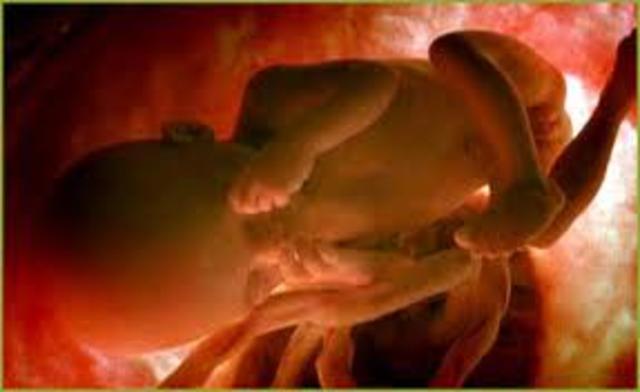

• Semana 26 a 29 de embarazo

Semana 26 a 29 de embarazo

Su sistema nervioso es capaz de controlar los movimientos respiratorios y la temperatura.S us movimientos on más activos, su estómago, intestino y riñones funcionan perfectamente. Todos sos órganos sensoriales están despiertos, los parpados y los ojos están completamente formados y comienzan a abrirse y cerrarse, comienza la freciencia cardiaca y a tener hipo.

• Semana 30 a 38 de embarazo

Semana 30 a 38 de embarazo

Ya se encuentra en la posición adecuada para el momento del parto, en la mayoría de los casos con la cabeza hacia abajo y los glúteos hacia arriba, su cráneo todavía no está completamente sólido. En la semana 38 él bebe ya está en condiciones de nacer